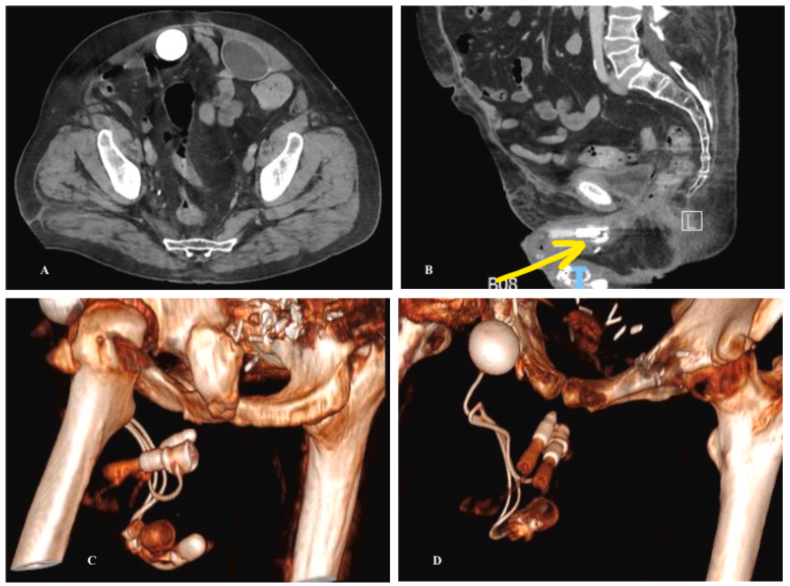

A case of malignant melanoma metastatic to the bladder. Presented with severe anemia secondary to intermittent gross hematuria. Perhaps not as rare as a glance at the literature may suggest! @FoleyAndFollies tinyurl.com/5mjumnrb